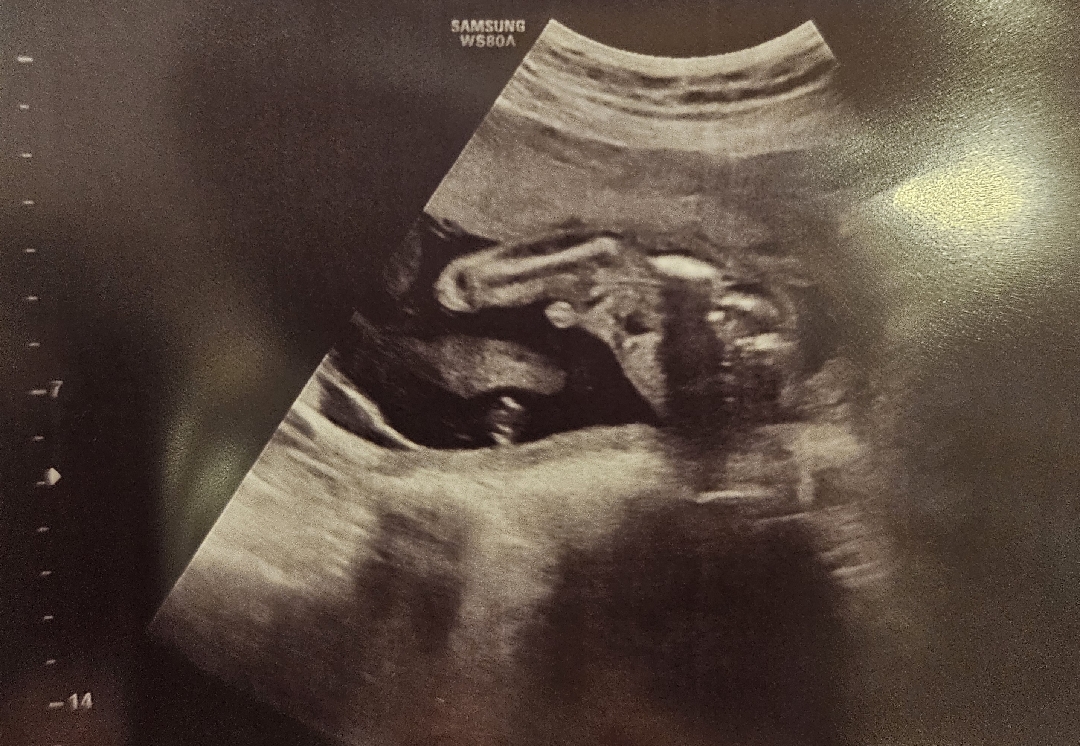

고추크기 이게 정상인가요?

19주차인데 고추가 너무 커보이는데 다들 이정도 크기인가요??

확대되서 그런거 같아요ㅋㅋㅋ 제 아들이 더 심하지 않나요..? 이게 태아가 맞나 싶어요..